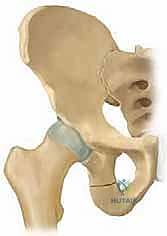

جراحة قطع عظم الحوض الثلاثي (TIO) هي إجراء جراحي يعيد توجيه التجويف الحقي لتحسين تغطية رأس الفخذ وعلاج خلل تنسج الورك، خاصة في الأطفال والمراهقين. يتم من خلال قطع عظام الحوض الثلاثة (الحرقفة، الإسك، العانة) لتمكين دوران التجويف الحقي حول رأس الفخذ، مما يزيد من استقراره ويقلل من خطر التهاب المفاصل المبكر.

من خلال إجراء قطوع دقيقة في عظام الحوض الثلاثة (الحرقفة، الإسك، العانة)، يتم تحرير التجويف الحقي بالكامل ليتم تدويره حول رأس الفخذ، مما يضمن استقراراً ميكانيكياً حيوياً للمفصل، ويمنع الخلع المتكرر، ويقي المريض من خطر الإصابة بالفصال العظمي (التهاب المفاصل التنكسي) المبكر الذي قد يستدعي زراعة مفصل صناعي في سن مبكرة.

لفهم أهمية جراحة (TIO)، يجب أولاً فهم التشريح المعقد لمفصل الورك. يُصنف مفصل الورك على أنه مفصل كروي حقي (Ball-and-Socket Joint). تتكون "الكرة" من رأس عظم الفخذ (Femoral Head)، بينما يتكون "التجويف" من الحق (Acetabulum) وهو جزء من عظم الحوض.

في الحالة الطبيعية، يحيط التجويف الحقي برأس الفخذ بشكل شبه كامل، مما يوفر ثباتاً هائلاً أثناء الأنشطة اليومية مثل المشي، الركض، وحمل الأوزان. تعمل الغضاريف الملساء التي تغطي كلا السطحين على تقليل الاحتكاك، بينما تحافظ الأربطة القوية على بقاء المفصل في مكانه.

في حالات خلل التنسج، يكون التجويف الحقي ضحلاً جداً (غير عميق بما يكفي) أو مائلاً بزاوية غير طبيعية. هذا يعني أن "الكوب" لا يغطي "الكرة" بشكل كافٍ. نتيجة لذلك:

بمجرد اكتمال هذه القطوع الثلاثة، يصبح التجويف الحقي (الكوب) منفصلاً تماماً عن بقية الحوض، مع بقاء إمداداته الدموية سليمة.

4. إعادة التوجيه والتدوير (Rotation & Redirection)

باستخدام أدوات خاصة، يقوم الدكتور هطيف بتدوير التجويف الحقي الحر في ثلاثة أبعاد (للأمام، وللخارج، وللأسفل) حتى يغطي رأس عظم الفخذ بشكل مثالي وميكانيكي سليم. يتم التحقق من الزاوية الجديدة فوراً داخل غرفة العمليات باستخدام جهاز الأشعة السينية المتحرك (C-arm).